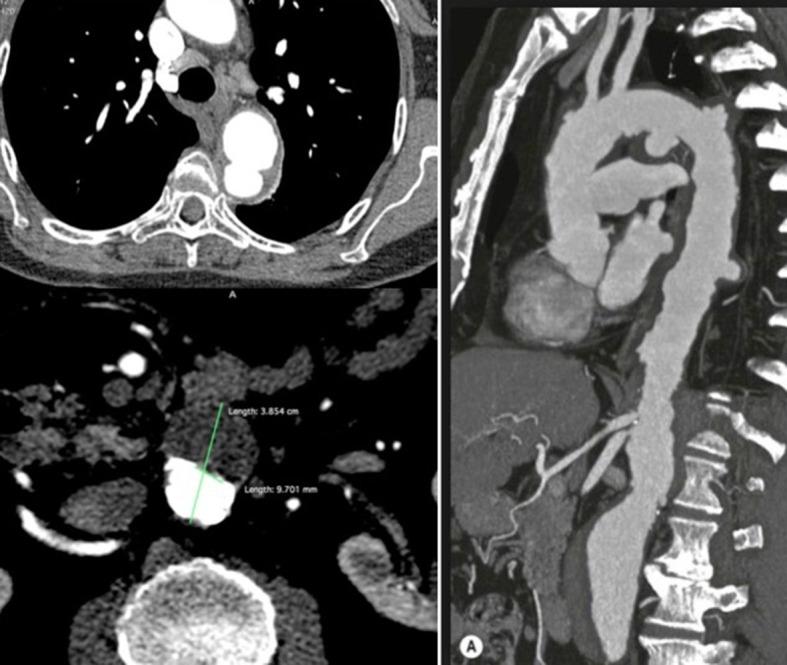

The natural histories of intramural hematoma (IMH) and penetrating atherosclerotic ulcer (PAU) are highly variable as they may progress to aneurysm formation, rupture, or dissection, or even resolve, in the specific case of IMH. Imaging plays an increasingly important role in clinical and surgical management of IMH and PAU. In contrast to ulcer-like projections, images of intramural blood pools have not been widely reported in CT studies of patients with IMH. Understanding the imaging characteristics and the natural course of each of these entities would help clinicians and surgeons to identify patients at greatest risk for bad prognosis and may improve outcomes. This paper discusses the pathophysiology of these entities, the controversies regarding their natural history, and the prognostic factors that should be identified in CT scans.

壁内血肿(IMH)和穿透性动脉粥样硬化溃疡(PAU)的自然病程差异很大,因为它们可能进展为动脉瘤形成、破裂或夹层,甚至在IMH的特定情况下自行消退。影像学在IMH和PAU的临床及手术管理中发挥着越来越重要的作用。与溃疡样突出不同,壁内血池的影像在IMH患者的CT研究中尚未得到广泛报道。了解这些病变各自的影像学特征和自然病程将有助于临床医生和外科医生识别预后不良风险最高的患者,并可能改善治疗结果。本文讨论了这些病变的病理生理学、关于其自然病程的争议以及CT扫描中应识别的预后因素。